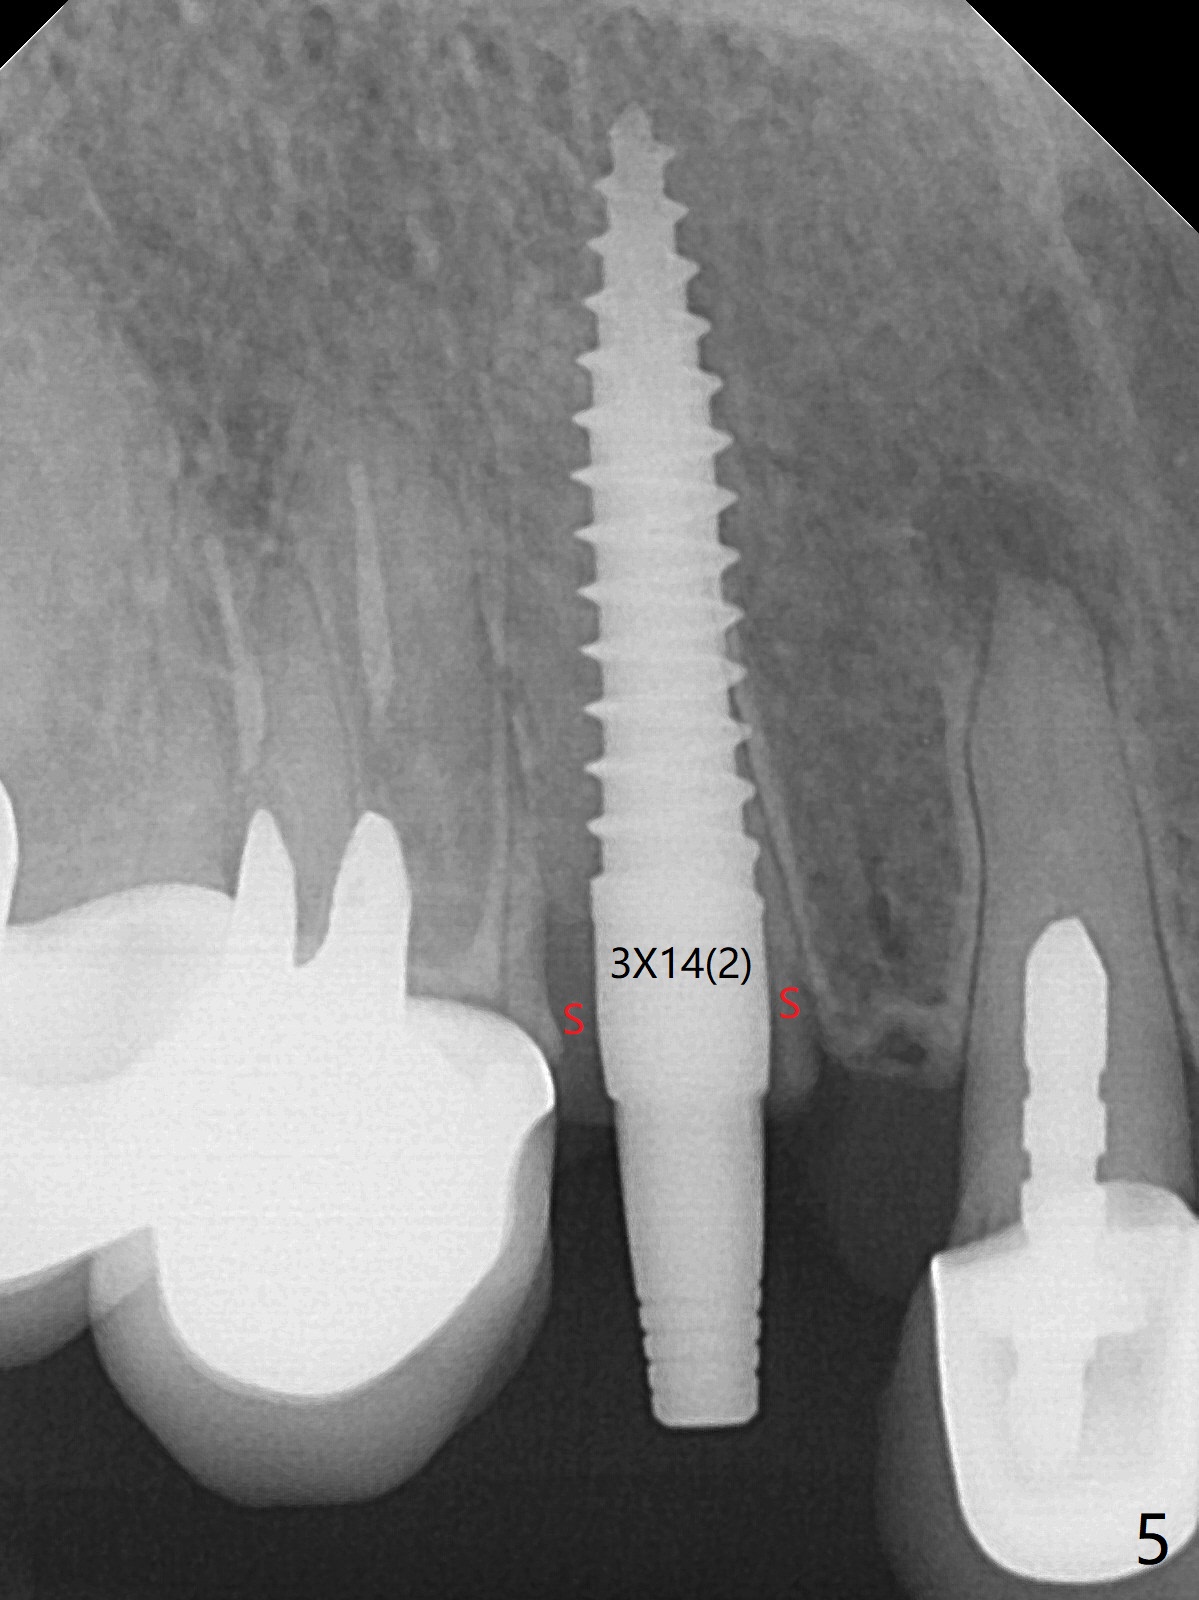

防止拔牙后颊侧骨板萎缩最有效方法是保留部分牙根,例如颊侧(外形象盾牌,简称盾,socket shield (S)),但是制备特别麻烦,尤其是上尖牙。60岁女右上3颊侧骨板隆起(图一至三:*),但是相当狭窄(上下方向),预计强行拔除,势必损失颊侧骨板,造成颊侧塌陷,准备保留盾,如图三红虚线,图六(术后3D长轴断面(十字架:植体))S代表。其实术中试图将整个牙根一起拔除,但是仿佛不行,只好静下心来分根,制备盾,不过困难重重,尤其是除去根尖(防止残余感染),最长外科裂钻似乎达不到根尖,取出后者,颊侧根尖骨板穿孔(图七:箭头)。然后腭侧钻洞(图四),当最后一个钻头保持原位时,在颊侧根尖穿孔处植入粘性骨粉(从牙槽窝口进入,原本粘性骨粉为了修复大面积颊侧缺损用(万一需要强行拔除)),然后才把一段式植体植入(图五),在其余空间填入骨粉,稍微制备基台,制作临时牙冠,最后在牙槽窝开口塞入PRF膜,衬里牙冠,不暂时取出牙冠,衬里相当于临时粘固剂。术后一个月牙根片段和临时牙冠维持良好的牙龈外形(图八,九);术后两个月病人嫌尖牙龈端太尖太长,临时牙冠龈端调整(图十,十一),但愿一个月后龈缘合乎病人期望。